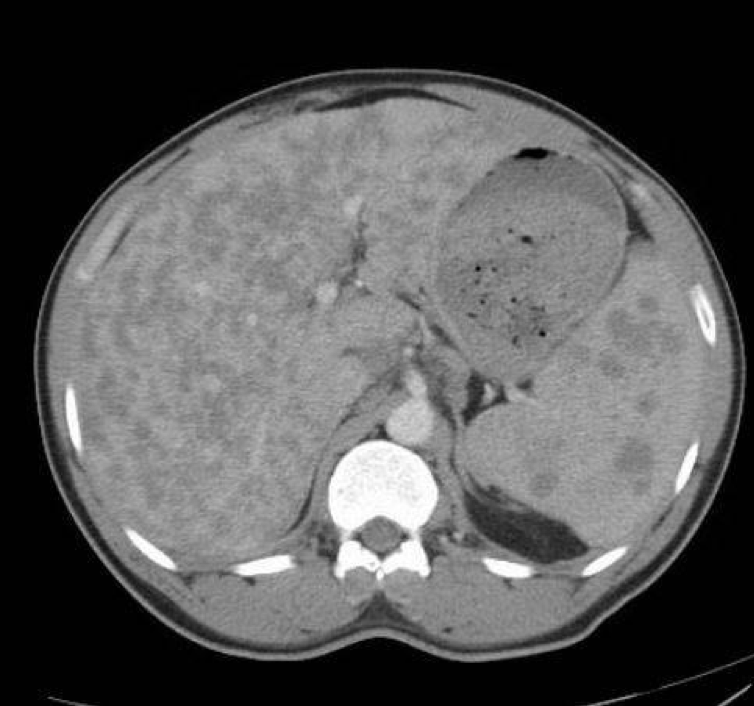

Figure 1.The CT scan of the abdomen and pelvis (Figures 2 and 3) showed an enlarged liver almost completely replaced by multiple low-attenuation lesions, none larger than 20 to 30 mm. The spleen was also enlarged, with multiple lesions measuring up to 20 mm. Extensive enlarged upper abdominal, periportal, and retroperitoneal lymph nodes were noted. These radiographic findings were suggestive of sarcoidosis or lymphoma.

Figure 3Further workup included tissue sampling, given the aggressive appearance of the lesions. The patient underwent a bronchoscopy with right paratracheal and subcarinal transbronchial needle aspiration, the results of which were negative for malignant cells. The acid-fast bacilli (AFB) smear was negative. The angiotensin-converting enzyme (ACE) levels were greater than 360 U/L (reference range, 9-67 U/L). In addition, records from a previous hospitalization in Italy showed a history of complete atrioventricular (AV) block. The imaging, tissue sample, and laboratory test results with clinical correlation were suggestive of sarcoidosis.

Of note, hepatic involvement occurs in most patients with sarcoidosis. Hepatic sarcoidosis is approximately twice as common in the African American population than in the white population.3-5 Approximately 50% to 65% of patients with sarcoidosis will have granulomas on liver biopsy, but only 5% to 15% of patients have symptomatic hepatic sarcoidosis.4,6,7 Most are asymptomatic and only have biochemical abnormalities such as elevated alkaline phosphatase and γ-glutamyltransferase levels. Hepatomegaly is noted in 5% to 15% of patients.3,4 Typical CT findings are hepatosplenomegaly and numerous hypodense nodular lesions ranging in size from 1 mm to 3 cm.8,9 Gastroenterological involvement is found in 1% of cases and mostly manifests as gastric ulceration or mural infiltration.10 Liver biopsy is recommended when laboratory test results show moderate or severe liver abnormalities of more than 3 times the upper limit of normal.11